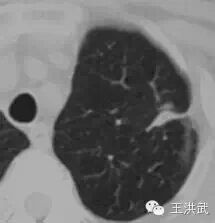

冷冻前肺内3cm(直径)肿块

冷冻10个月后,肺内肿块基本消失